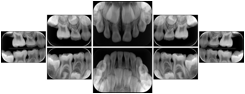

Intra-oral radiography typically involves acquisition of multiple images of various parts of the dentition. Many digital radiographic systems offer customized templates that are used for displaying the images in a study on the screen. These templates may also be referred to as mounts or view sets. The Structured Display Object represents a standard method of encoding and exchanging the layout and intended display of Structured Displays. A structured display object created in this manner could be stored with a study and exchanged with images to allow for complete reproduction of the original exam.

In most standard cases, images are oriented in structured layouts. These structured displays are useful to be shared between providers for reference purposes.

Table OO.1.1-1 shows structured display standard templates, where Viewset ID is based on the Japanese Society for Oral and Maxillofacial Radiology (JSOMR) classification provided by JIRA (Japan Medical Imaging and Radiological Systems Industries Association, www.jira-net.or.jp). Expected or typical teeth to be imaged location, region and designation codes are based on ISO 3950-2010, Dentistry - Designation system for teeth and areas of the oral cavity. For all the hanging protocols listed in OO.1.1-1, the value to use for Hanging Protocol Creator (0072,0008) is "JSOMR" and the value to use for Hanging Protocol Name (0072,0002) does not include "JSOMR" (e.g., "DL-S001A", not "JSOMR DL-S001A").